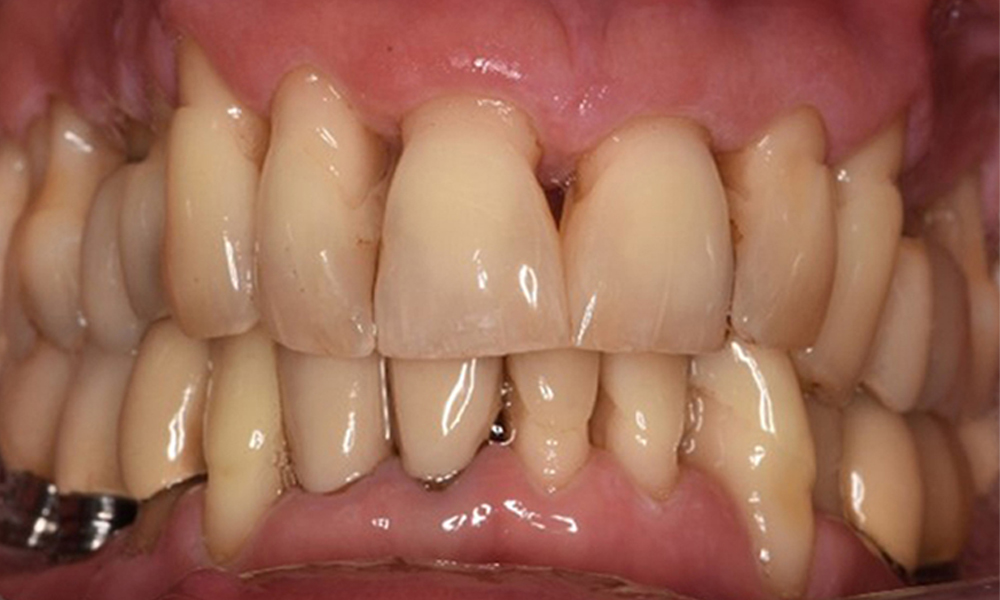

52-годишен пациент се явява на профилактичен преглед. Пациентът няма хронични заболявания и не приема никакви лекарства. Претърпял е различни дентални лечения и също така има две активни кариозни лезии. Освен това има четири импланта (2-ри, 3-ти и 4-ти квадрант). Установява се, че има ранно пародонтално заболяване (стадий IV, степен В). Състоянието на пародонта е стабилно, като дълбочина на сондиране (ST) от 5 mm се проявява само при импланта в област 36. Установен е и гингивит.

Хигиената на устната кухина и сътрудничеството от страна на пациента са много добри (виж снимката „изглед отпред“). Необходими са само повтарящи се инструкции и мотивация за поддържане на орална хигиена.